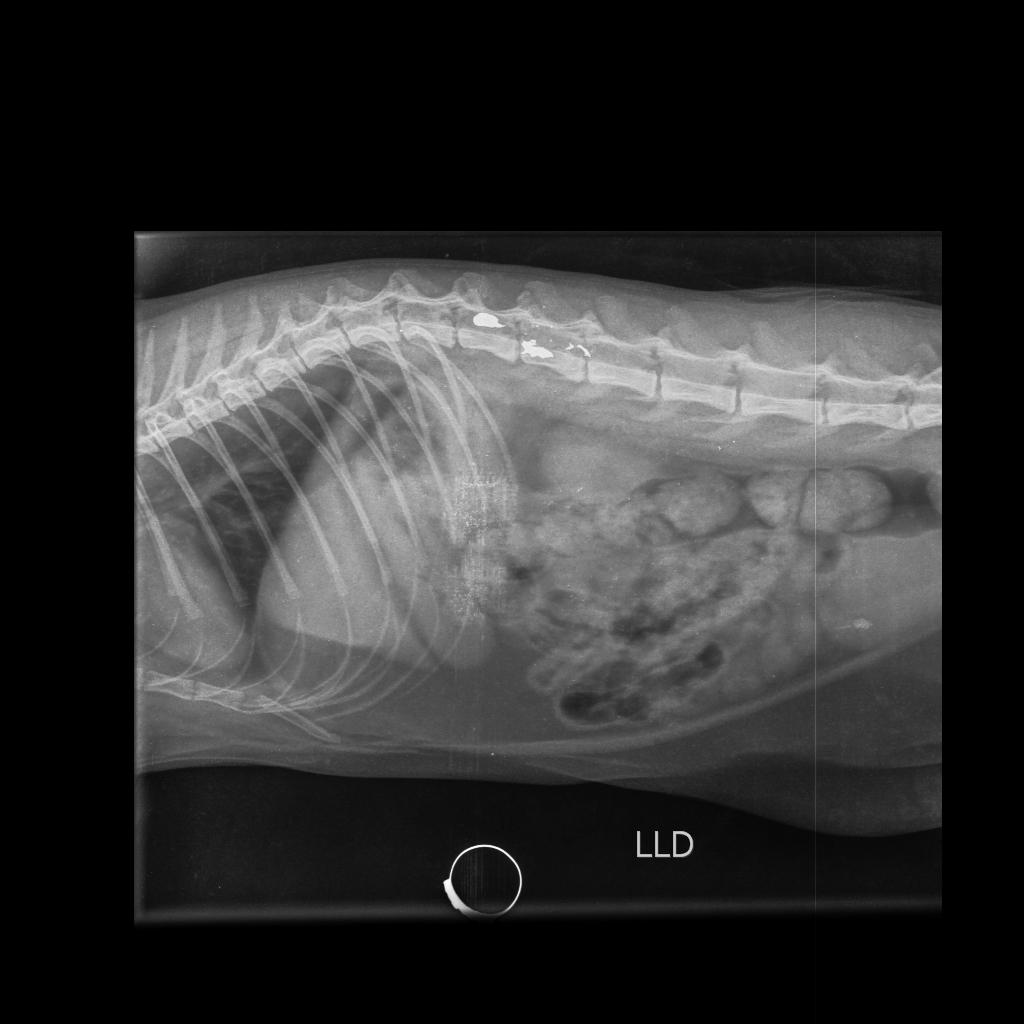

A Polícia Civil investiga mais um caso de agressão contra animal em Toledo. Na madrugada de terça-feira (03), por volta das 0h07, uma gata foi atingida por um disparo no bairro Jardim La Salle.

De acordo com o delegado Dr. Alexandre Macorin, os proprietários do animal já foram ouvidos e a gata está sendo submetida a cirurgia. Testemunhas também foram identificadas, e o provável autor do disparo deverá ser ouvido e interrogado nas próximas horas.